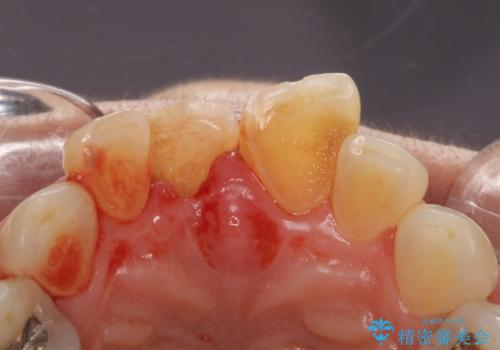

- 転んで前歯が折れたとのことで来院されました。

検査の結果、歯は大きく折れておらず、骨の中に埋め込まれていた状態であったため、部分矯正で歯を引っ張り出していきます。

ぶつけて埋まってしまった歯は、場合によって矯正治療で引っ張り出すことで保存することができます。

今回は歯の神経が死んでしまっていたため、根管治療後に被せ物を装着して見た目の綺麗さを回復しました。